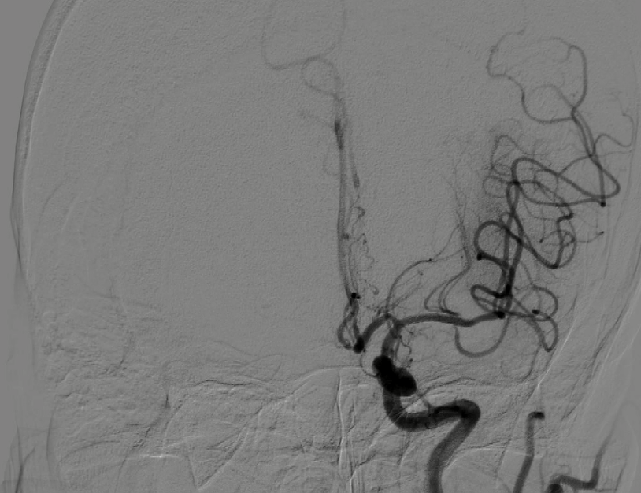

导引导管到位,导丝通过病变。

导丝怎么扩【载药时代 球扩天下】NOVA DES®颅内药物洗脱支架在颅内富穿支区域使用体会二例!_https://www.jmylbn.com_新闻资讯_第31张

支架释放后影像。

导丝怎么扩【载药时代 球扩天下】NOVA DES®颅内药物洗脱支架在颅内富穿支区域使用体会二例!_https://www.jmylbn.com_新闻资讯_第32张

导丝怎么扩【载药时代 球扩天下】NOVA DES®颅内药物洗脱支架在颅内富穿支区域使用体会二例!_https://www.jmylbn.com_新闻资讯_第33张

导丝怎么扩【载药时代 球扩天下】NOVA DES®颅内药物洗脱支架在颅内富穿支区域使用体会二例!_https://www.jmylbn.com_新闻资讯_第34张

术后影像及检查

影像结论:狭窄解除。